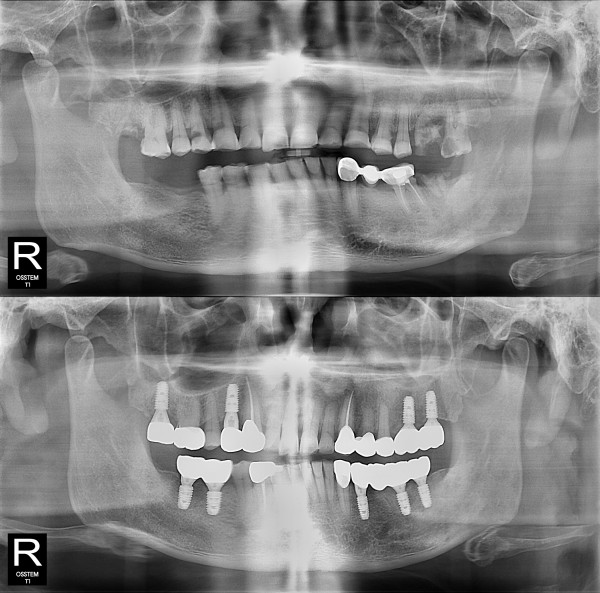

种植牙

局部种植牙